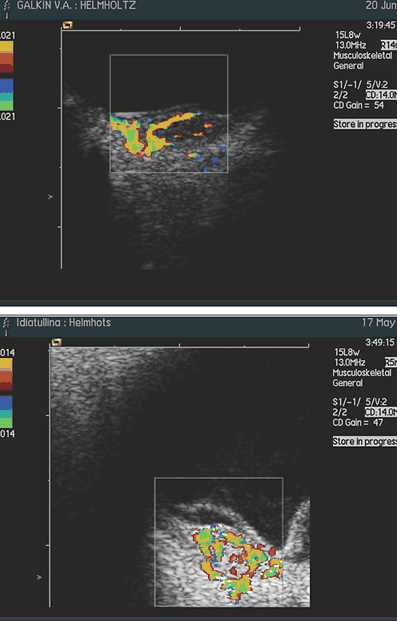

При

исследовании в режиме ЦДК во всех случаях, независимо от размеров отграниченной

гемангиомы, выявлено равномерное распределение новообразованных сосудов по всей

ее толщине и площади. Визуально кровоснабжение гемангиомы осуществляется за

счет сосудов хориоидеи: сосуды сетчатки не участвуют в ее питании (рис. 3, 4)

Только при юкстапапиллярной локализации (3 случая) опухоль получала двойное

кровоснабжение – за счет сосудов хориоидеи и ЦАС (рис. 5).

Рис.

3, 4: Цветовое допплеровское картирование гемангиомы макулярной локализации

5. Цветовое допплеровское картирование юкстапапиллярной гемангиомы хориоидеи